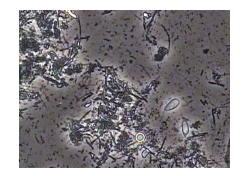

歯垢(プラーク)の中にいる生きた細菌を染色せずに(殺さずに)、リアルタイムでの菌種・活動性(動き)を観察できる特殊な顕微鏡です。

歯周病菌(スピロヘータなど)や虫歯菌、カビ(カンジダ)などの種類・量・活動性を確認し、

歯周病や口臭のリスク診断補助、治療効果判定、患者様への口腔衛生についてご提案させて頂きます。

健康な口腔内の「常在菌」と「病原菌」のバランスを可視化し、

歯周内科治療などの適切な治療方針決定に役立てています。